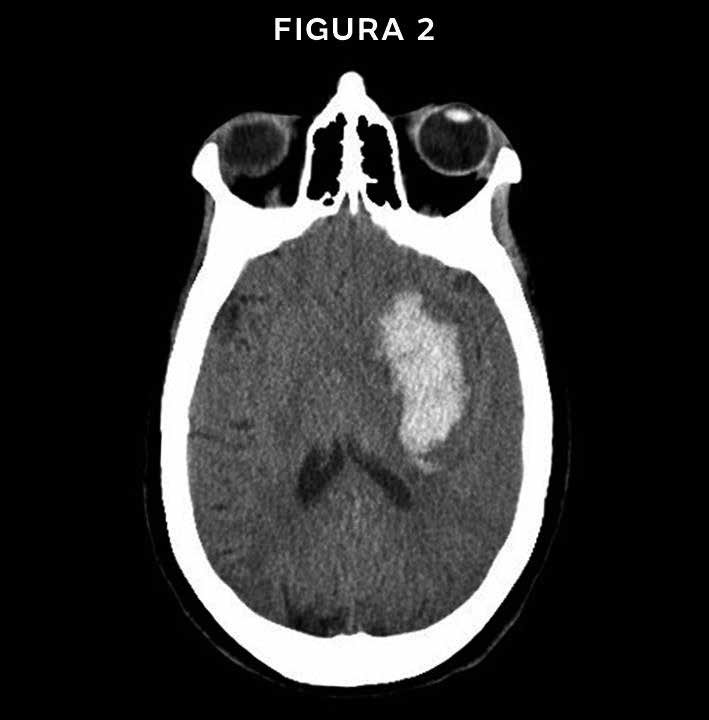

Voltando a TC do enunciado (FIGURA 1), o que encontramos? Observem uma imagem hiperdensa (branca) entre os sulcos (setas amarelas), uma região

que deveria ser hipodensa (preta), pois é preenchida por liquor. Essa imagem hiperdensa representa sangramento difuso entre os sulcos. Não temos imagem hiperdensa biconvexa, para pensarmos em hematoma epidural, nem imagem hiperdensa que acompanha a convexidade cerebral, para considerarmos o diagnóstico de hematoma subdural. Sendo assim, o nosso diagnóstico é de uma hemorragia subaracnóidea traumática. Alguns candidatos responderam hematoma intraparenquimatoso, mas vejam como a imagem de uma coleção parenquimatosa é bem diferente da apresentada no enunciado (FIGURA 2).